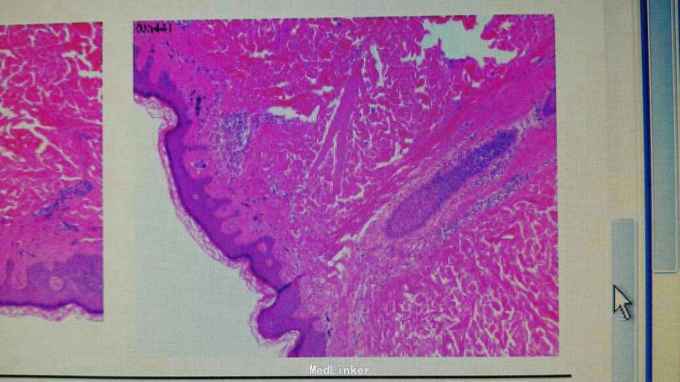

右额部、左肩胛上、左肩胛下各见一黄豆至蚕豆大灰蓝色斑片,色素呈网状分布,边界清。 切除左肩胛上皮损行病理活检示:蓝痣。

诊断:蓝痣 治疗:分别手术切除